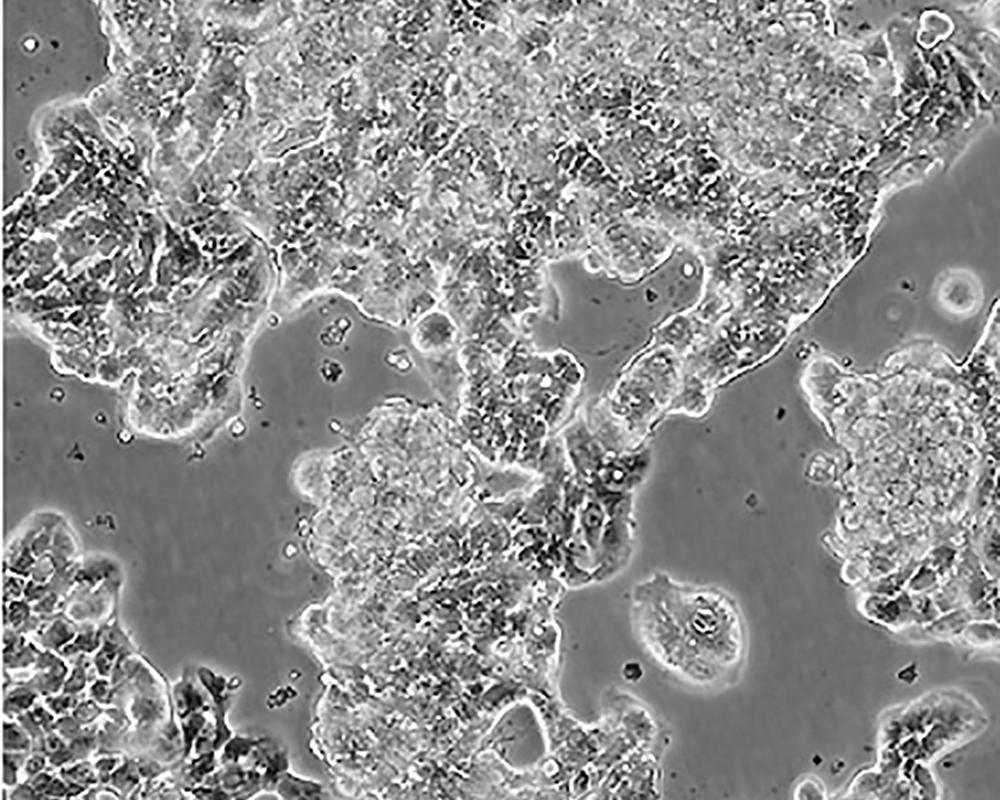

ZR-75-1 [ZR751]

產品名稱 ZR-75-1 [ZR751]

中文名稱 人乳腺癌細胞

組織來源 浸潤性導管癌;腹水轉移;女性

形態特征 epithelial

細胞描述 該細胞產生高水平的黏液素MUC-1 mRNA,低水平的MUC-2 mRNA,但不表達MUC-3基因;表達雌激素受體。